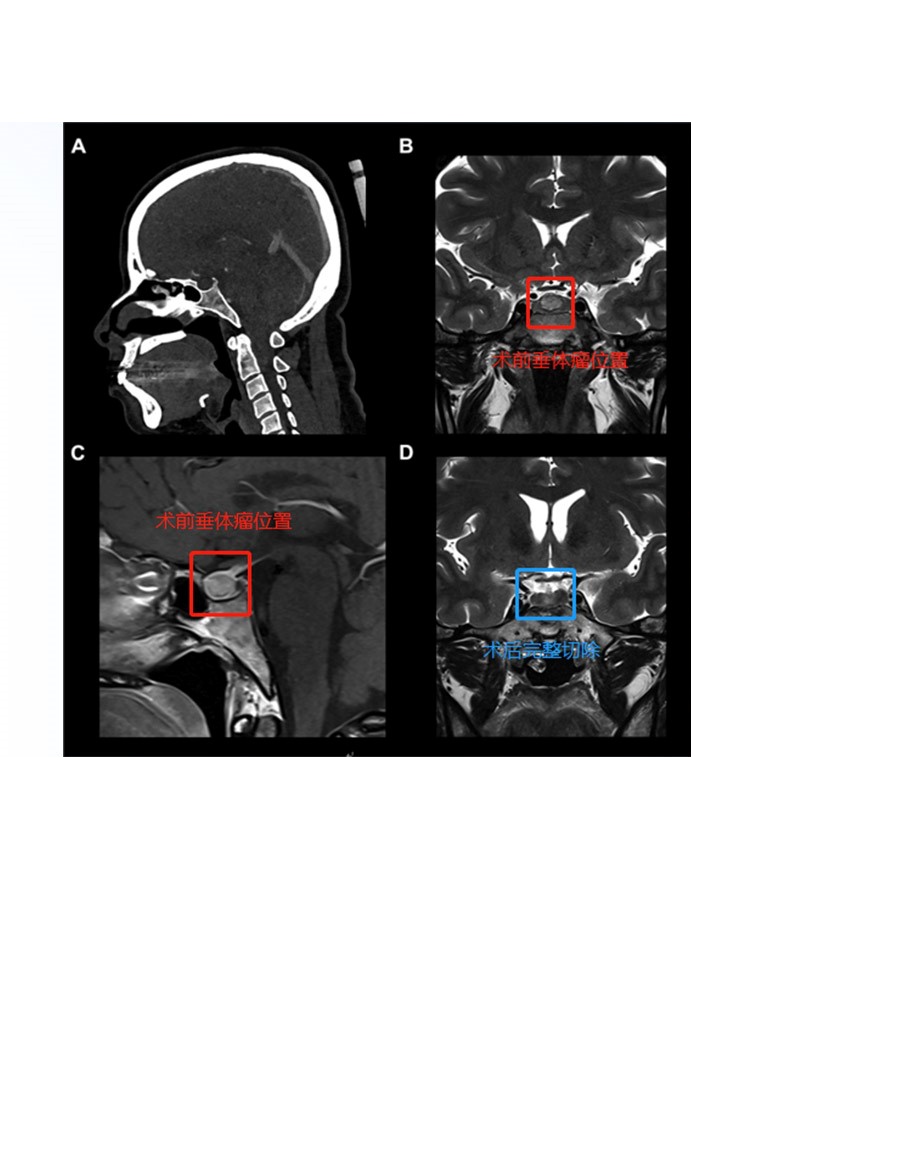

法国Sebastien Froelich教授垂体瘤全切手术案例一则

一名37岁的法国女性被发现有位于蝶鞍中央的9mm垂体瘤后,同样选择的也是神经内镜经鼻单鼻孔切除术,医生采用的是当前热门神经内镜“筷子手法”使肿瘤得以完整切除,目前正在进行相关内分泌治疗,手术后3年垂体瘤没有复发的迹象,无其他并发症。